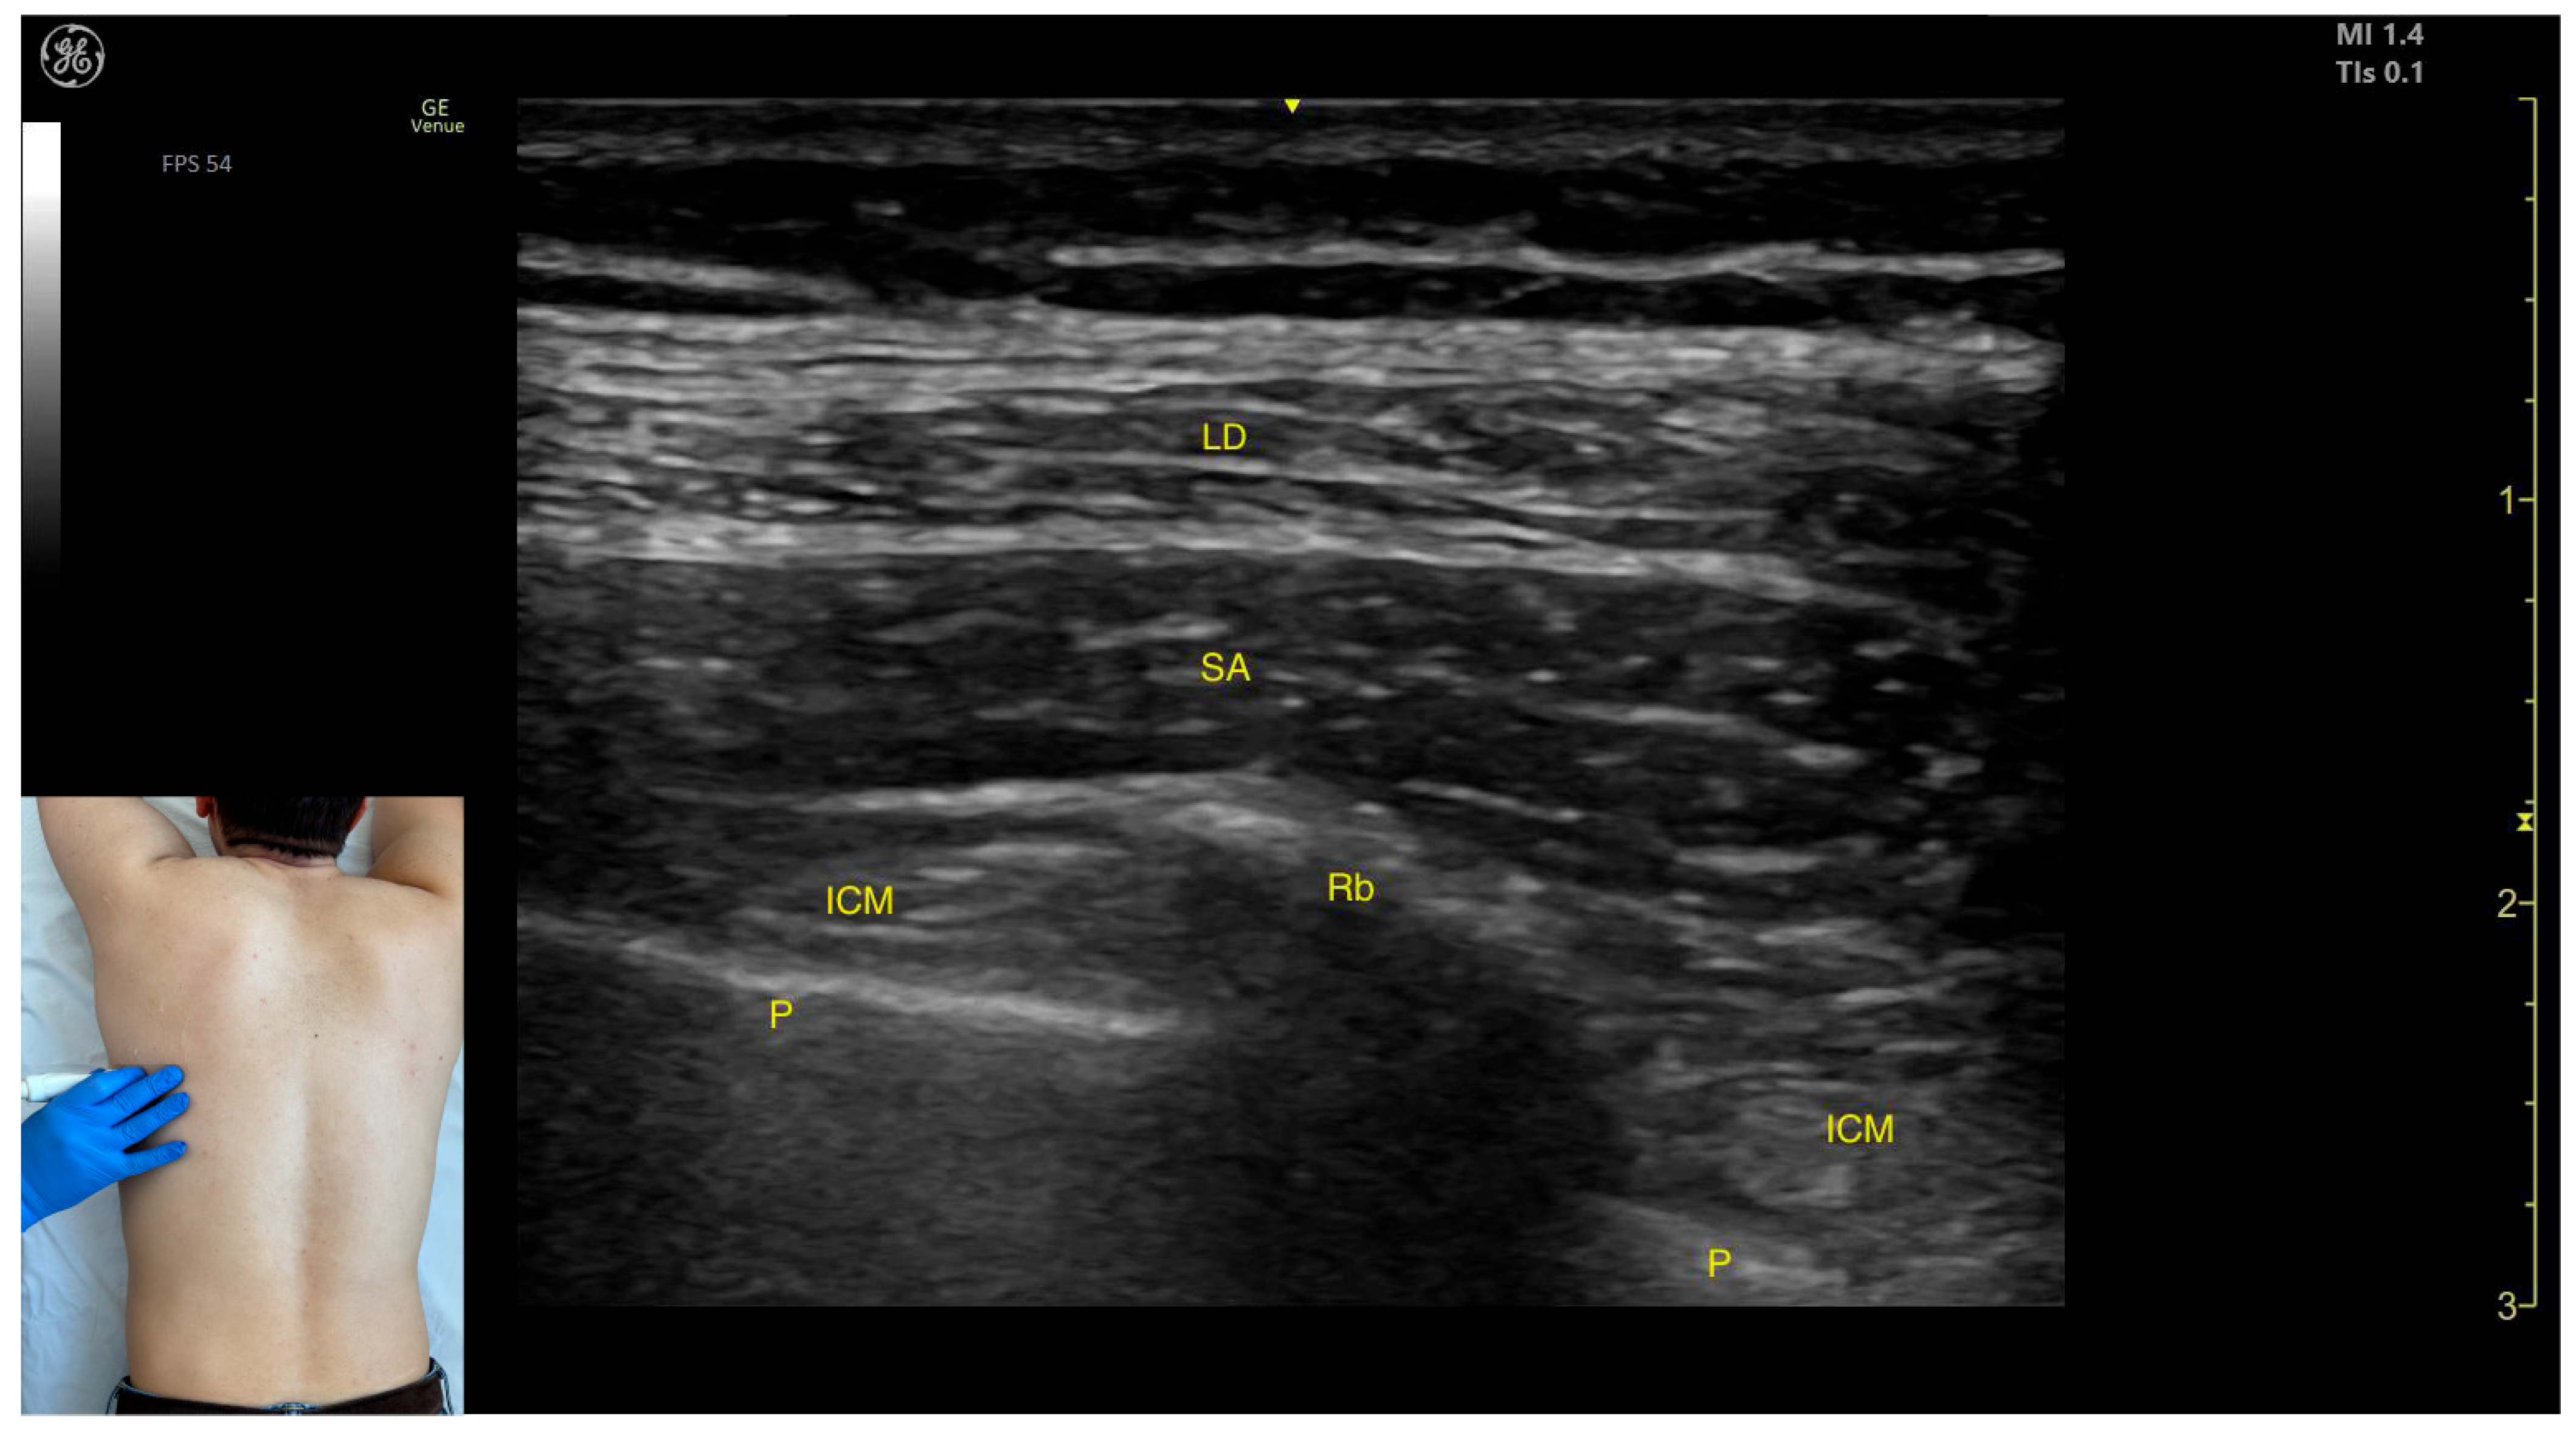

2.1.2. Ultrasound Identification

2.1.3. Key Ultrasound Landmarks

- Muscle position: The LD is the most superficial muscle mass on the posterior surface of the trunk at this level.

- Muscle morphology: It has a more pronounced fascia that separates it from the subcutaneous plane than the fascia that separates it from the intercostal muscle (ICM) muscle during BoNT-A injections.

- Dynamic evaluation: Scanning proximally (~5 cm) shows a reduction in the size of the LD and the appearance and enlargement of the serratus anterior (SA) muscle beneath it. Contraction is visible with extension, adduction, and medial rotation maneuvers of the humerus at the shoulder joint [7]. At this level the LD has a more pronounced fascia that separates it from the subcutaneous plane and the SA muscle.

2.1.4. Clinical Implications and Injection Strategy